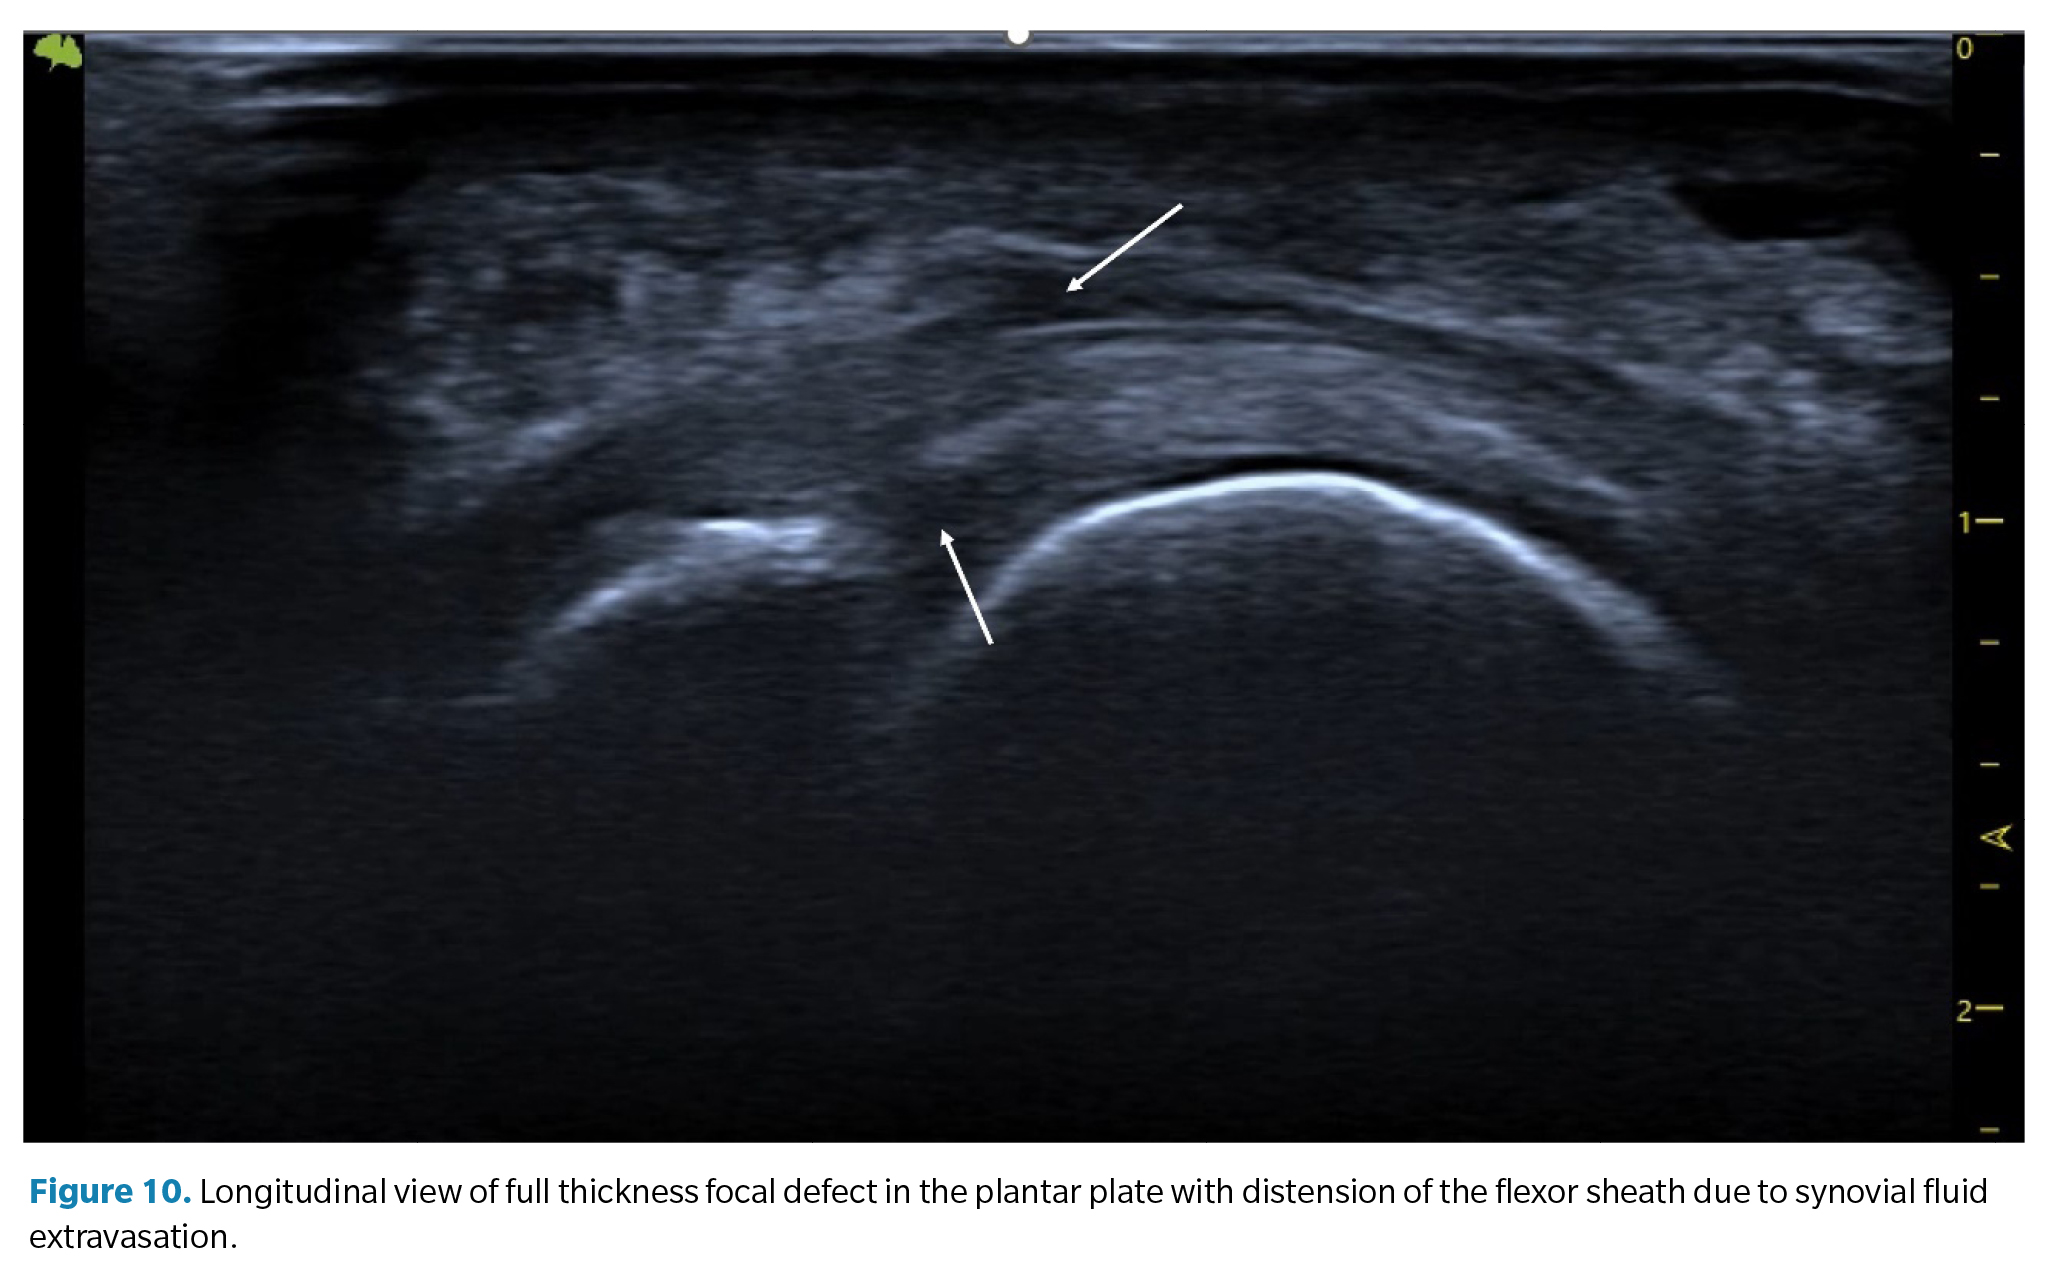

Indirect ultrasound findings

1. Plantar or dorsal joint fluid (synovitis). Synovial effusion. Since the plantar plate forms the plantar closure of the joint capsule, tears in the plate can lead to a significant increase in synovial fluid, which manifests as a detectable synovial effusion both dorsally and plantarly. In some cases, this fluid can leak into the flexor tendons, creating a hypoechoic halo around them resembling the characteristic image of tenosynovitis with distension of the tendon sheath (Figure 10).